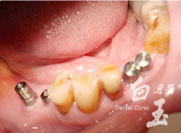

植入植體

治療後